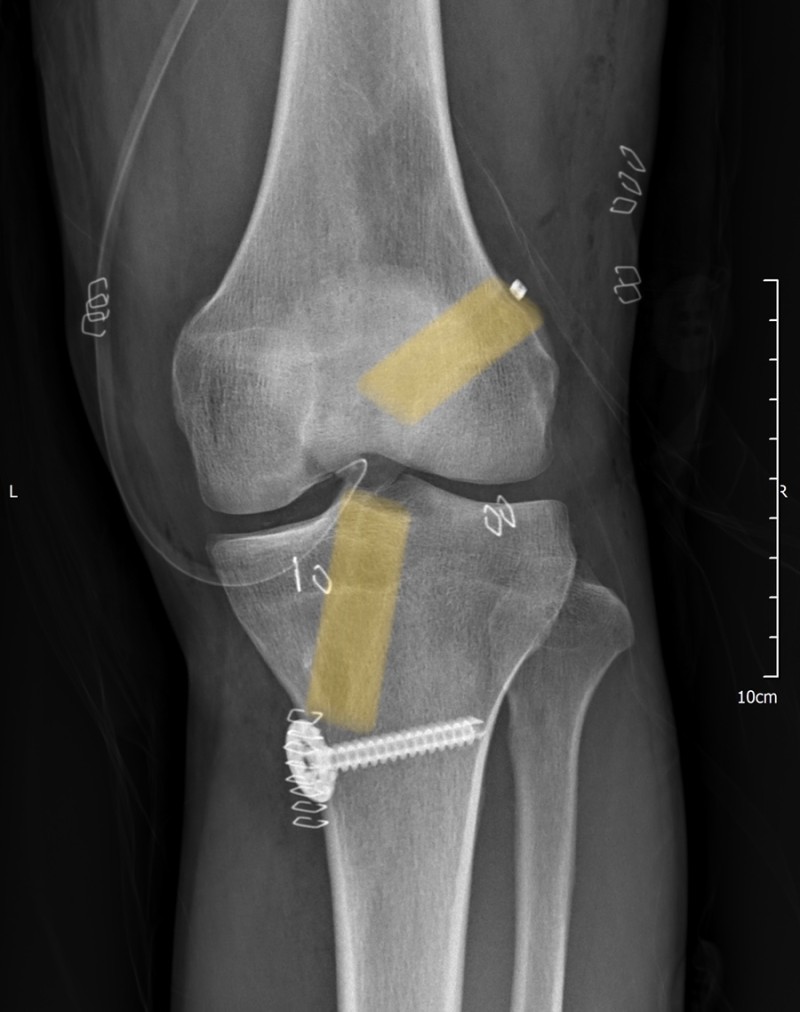

실제 본원 수술 사례

최근에 스키 및 축구 등으로 전방십자인대 파열되신 분이

여러분 오셔서, 지난주엔 두 건의 전방십자인대 재건술을

하였습니다.

Outside-in 술기를 통해 시행하였고,

1. 좌측 슬관절 전방십자인대 파열, 40대 남성

2. 좌측 슬관절 전방십자인대 파열, 30대 남성

두분 모두 XR 상에서 해부학적으로 좋은 위치에

터널이 형성되었음을 확인할 수 있습니다.